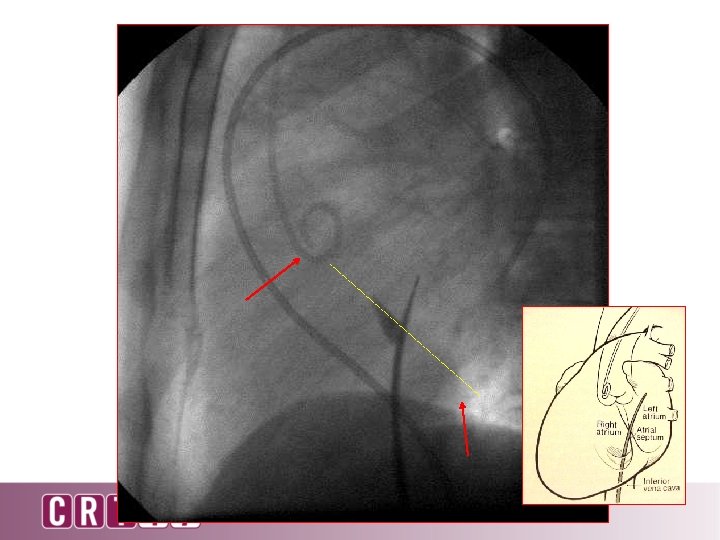

90 o lateral

90 degree lateral